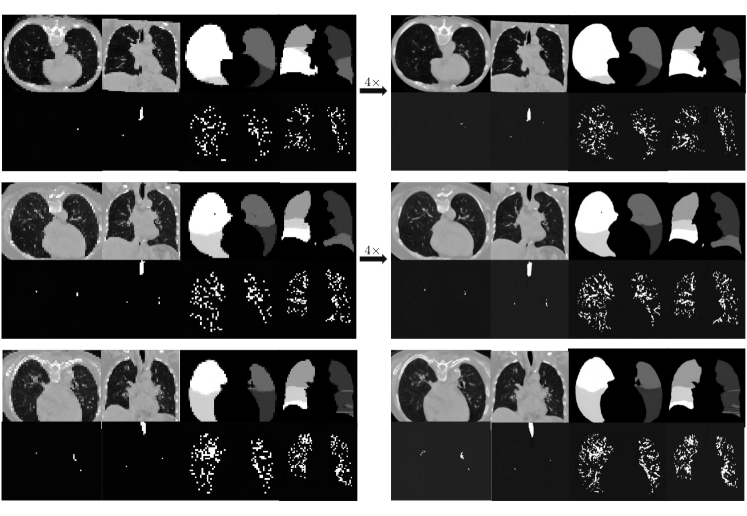

Super-Resolution Module

In Fig. 7, we present the super-resolution module as the conditional diffusion model from the low-resolution volumes.

Refer to caption

Figure 7: This figure shows the examples of our super-resolution results.

Figure 8: Results of super-resolution. Top row: generated low-resolution image. Second row: generated high-resolution image after super-resolution.